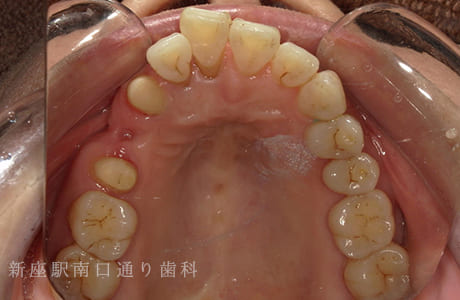

CASE.03

右下6番が破折抜歯後に

フルジルコニアブリッジで修復した症例

- 主訴

- 歯がないところを治したい

- 治療法

- 右下にフルジルコニアブリッジで修復

- 治療期間

- 1ヶ月半

- 費用

- ¥240,000(税込)

右下6番が破折し抜歯後にフルジルコニアブリッジで修復したです。

【リスク・副作用】

過度の咬合や衝撃で割れることがあります。治療直後は歯や歯茎に一時的な違和感や痛みが出ることがあります。